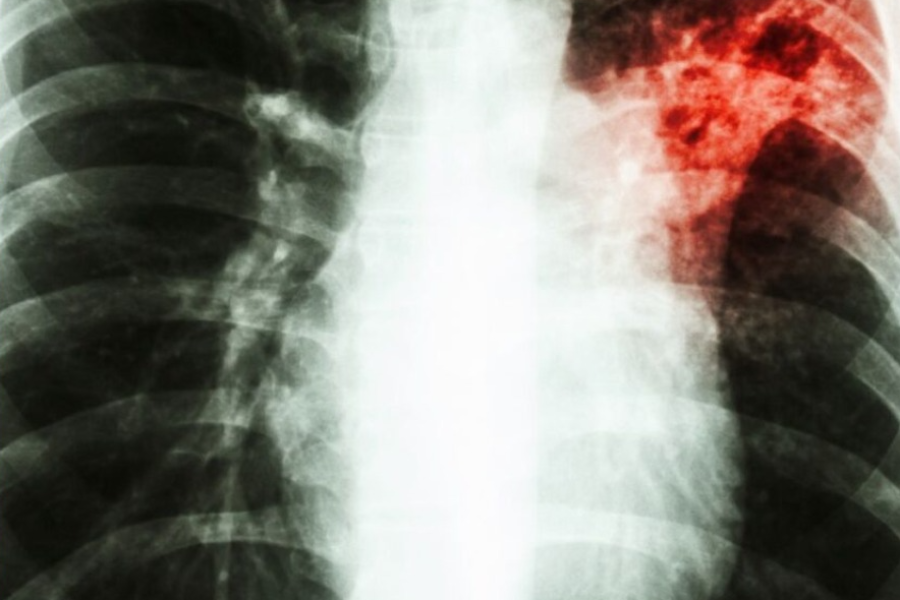

Relação entre diabetes e tuberculose preocupa OMS | Foto: Reprodução/Internet

A tuberculose, é uma infecção bacteriana que afeta principalmente os pulmões e tem sido uma das principais causas de morte no mundo, especialmente em países de baixa e média renda. Ao mesmo tempo, o diabetes, que compromete a capacidade do corpo de regular os níveis de açúcar no sangue, está em ascensão global, em parte devido ao aumento do sedentarismo e da má alimentação. Quando combinadas, essas duas condições podem representar sérios riscos à saúde.